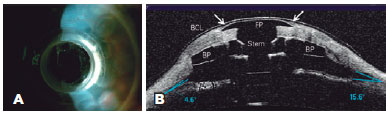

Thinning and gap formation (melting) of a corneal carrier graft was observed in 6 (55%) of the 11 eyes (Figures 1 A and 2). A clinically detectable gap between the corneal carrier graft and KPro was observed by slit lamp biomicroscopy in 3/11 (28%) eyes. Suspected thinning of the graft, characterized by the presence of small air bubbles between the donor cornea and KPro edge, was observed in 1/11 (9%) eye.

Retroprosthetic membrane formation was observed in 63% (7/11) of the eyes (Figures 1 B and 2), all of which were retro-backplate membranes, while retro-optic membrane formation was observed in 71% (5/7). Notably, all eyes with sterile corneal necrosis presented with a retroprosthetic membrane (Table 1). Most of the eyes (91%, 10/11) had some degree of peripheral anterior synechiae and angle closure (mean, 233.18º or 8.0 clock hours; range, 135-360º or 4.5-12 clock hours; SD, 118.74º) (Figure 2). Other less common findings were epithelial cyst formation and epithelial growth over the KPro optic surface (Figures 3 A and 3 B).